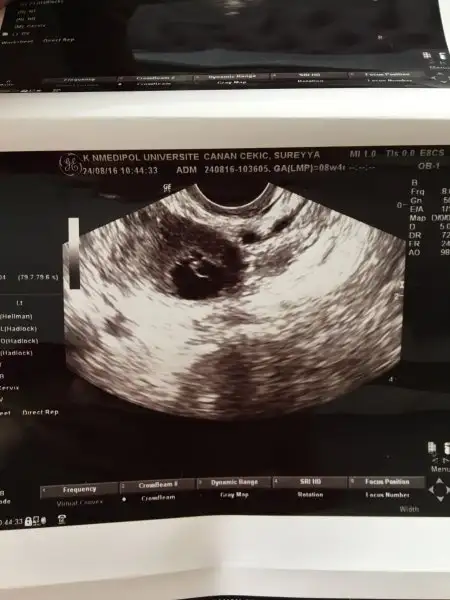

Hımm doktor bebek solda mi demişti öyleyse benim ki de sağda :) oy annesi yesin onu :)))öyle değildi benimki farklıydı :) ama eşim videomu cekmişti benim hastanede. kalp atışlarını duymak için. burdan videoyu size yollamak isteirm yollanabiliyorsa. benim sağımda kistim var, solumda bebek. monitorden bakınca kist solda gözüküyor yani tam tersi.

sana 7 ahftalıkken fotomu yolluyorum. bak kağıtta sağ yukarı tarafta. :) ama esasen solumda. kağıttaki soldaki de kocaman bir kist :)Hımm doktor bebek solda mi demişti öyleyse benim ki de sağda :) oy annesi yesin onu :)))

sana 7 ahftalıkken fotomu yolluyorum. bak kağıtta sağ yukarı tarafta. :) ama esasen solumda. kağıttaki soldaki de kocaman bir kist :)Eki Görüntüle 1876890